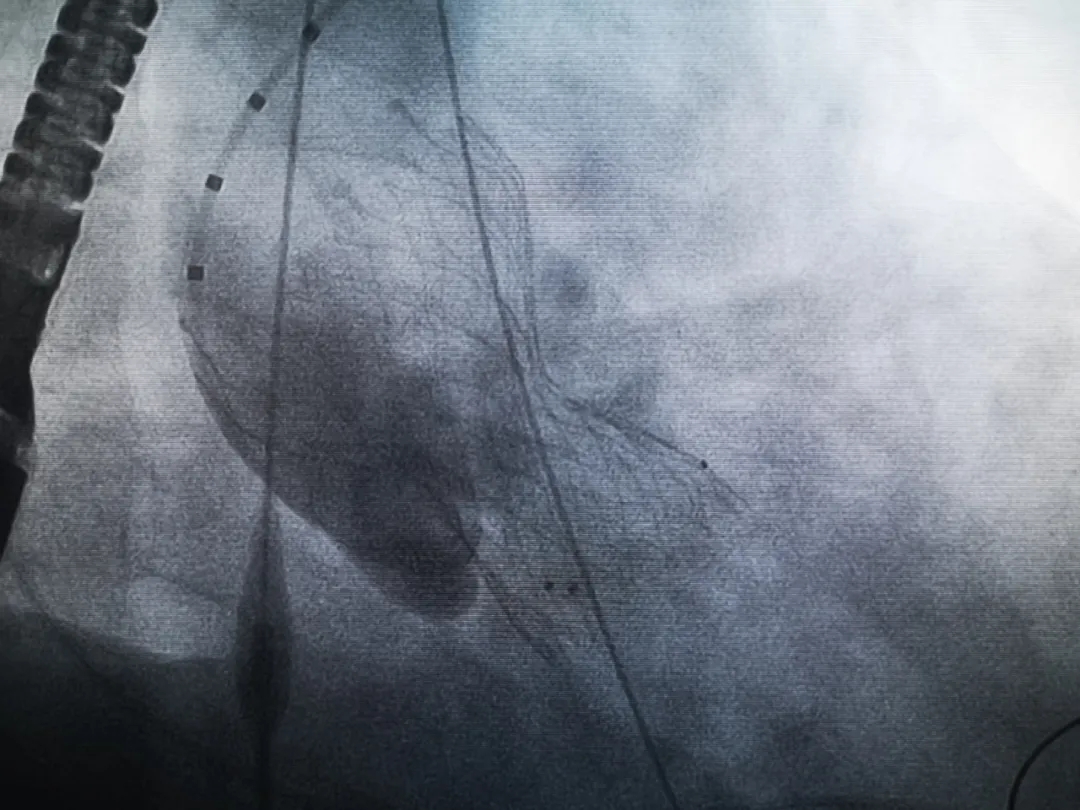

手術(shù)過程緊張而有序,心臟沒有停跳,也沒有太大的血壓波動;球囊擴張的恰到好處,瓣膜釋放之后超聲醫(yī)生的評估是至關(guān)重要的,因為我們提前就準備了后擴張,也準備了瓣中瓣,甚至還準備了瓣周漏封堵。所幸的是,超聲診療中心劉夢梅醫(yī)生說:沒有返流、沒有瓣周漏,瓣膜形態(tài)良好,跨瓣壓差約17mmHg(相較于術(shù)前的87mmHg還是可以接受的)。瓣膜置入的成功并不是慶祝的時候,從戰(zhàn)場撤退仍然需要謹慎。由于王子特別胖,腹股溝區(qū)脂肪尤為肥厚,在股動脈插管拔除、確認搏動正常之后,便逐層縫合。同時為了美觀、縫合之后不至于鼓個包出來,我們又仔細剪除了部分脂肪。術(shù)后次日,王子便可以下床活動了。